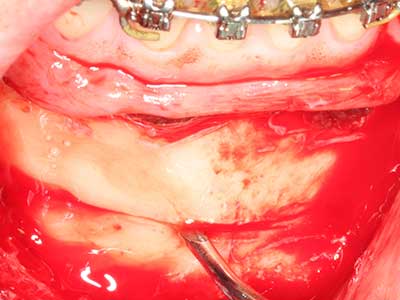

As shown in the past, basically any bone surgery procedure represents a possible indication for piezo surgery. Thus preparation of the mobile segment in distraction osteogenesis (Fig. 23-25) and sandwich osteotomy uses special attachments without endangering the blood supply to the crestal section, which is essential for the success of both techniques (Gonzalez-Garcia, Diniz-Freitas et al. 2008).

Purely orthodontic indications include orthognathic surgery, genioplasty (Fig. 27-30) and orbital decompression in patients with advanced endocrine orbitopathy as a result of Basedow’s disease (Ponto, Zwiener et al. 2014). Piezo devices are also used in maxillofacial surgery and to remove tumours at the base of the skull in various hospitals.